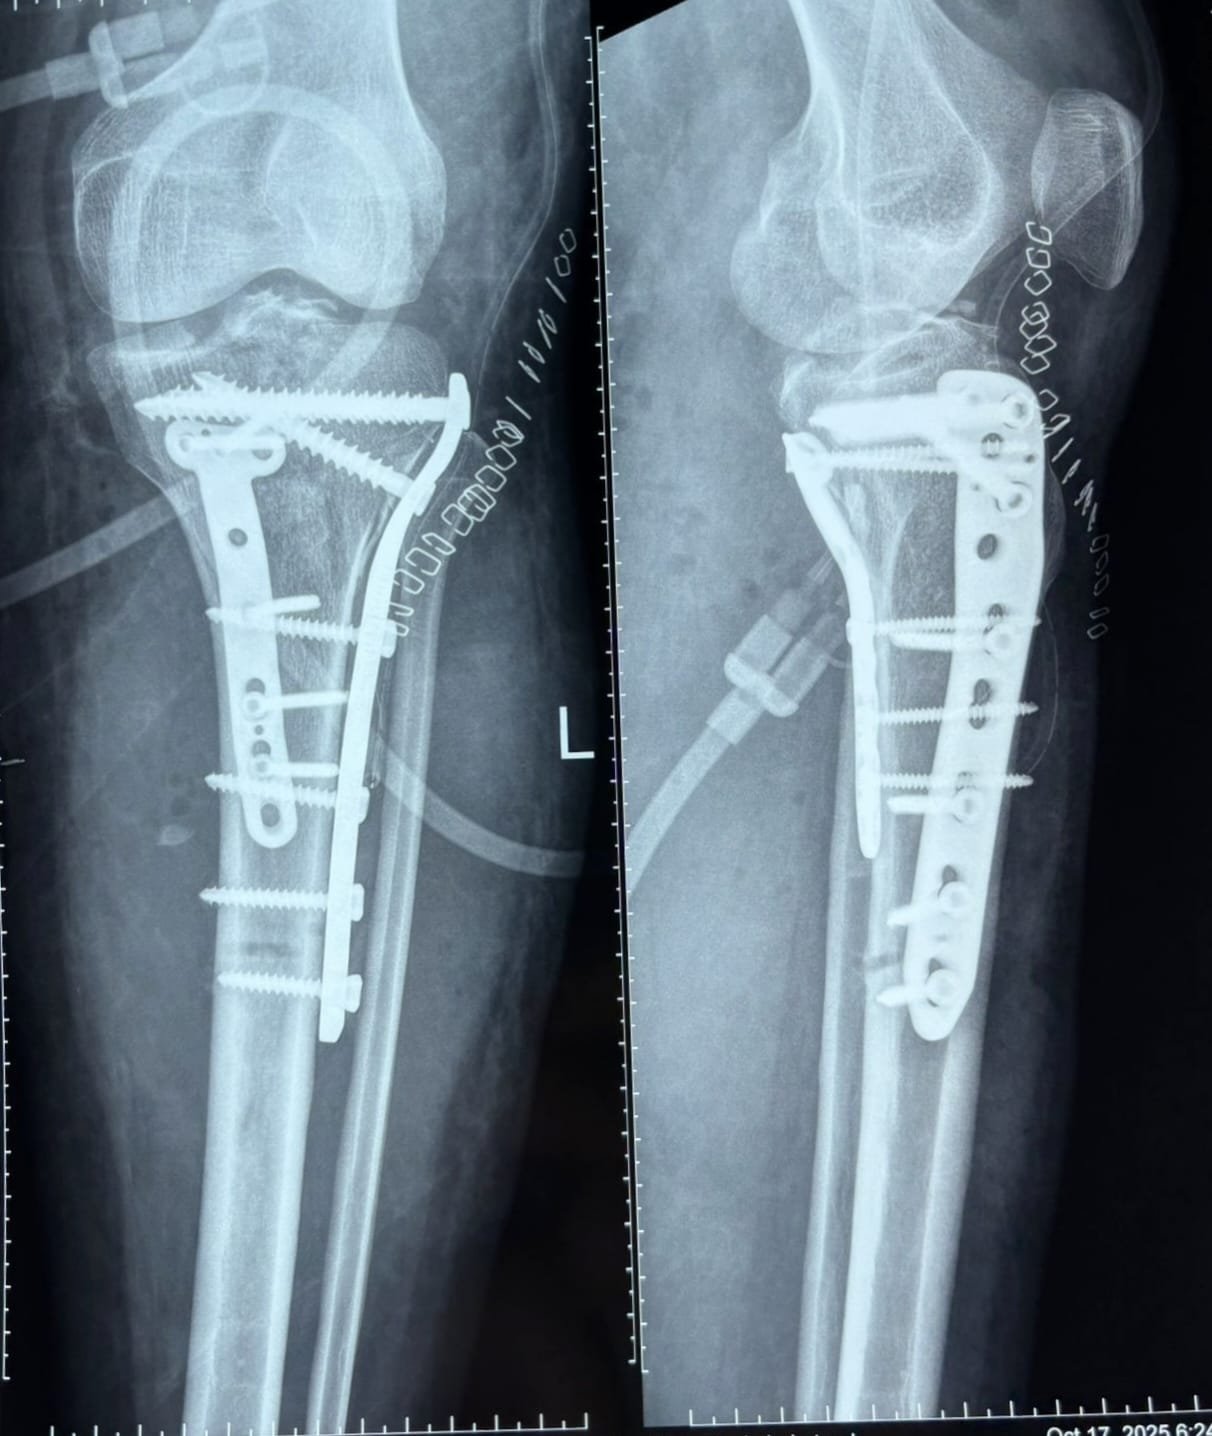

Fracture Care (Orthopedic Trauma):

◆ Expert management of orthopedic fractures, including complex traumatic and intra- articular fractures

◆ Surgical fracture fixation in absolutely indicated cases.